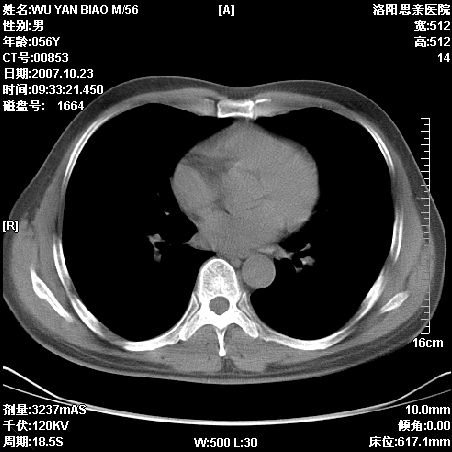

标题: CT10160:M56Y,体检发现,病人无不适,病人随访中 [打印本页]

标题: CT10160:M56Y,体检发现,病人无不适,病人随访中

后上纵隔占位,与肺交界清,宽基底附着脊柱,密度均匀,局部骨质无明确改变.

考虑;神经源性肿瘤,---起源交感n链?,不除外肠源性囊肿.

1、病灶在后纵隔脊柱旁沟内,此处是神经原性肿瘤的好发部位

2、病灶边缘光滑整齐,更说明病灶来于纵隔,由于有胸膜的包裹所以才导致这么光滑的边缘

3、病灶内的密度均匀